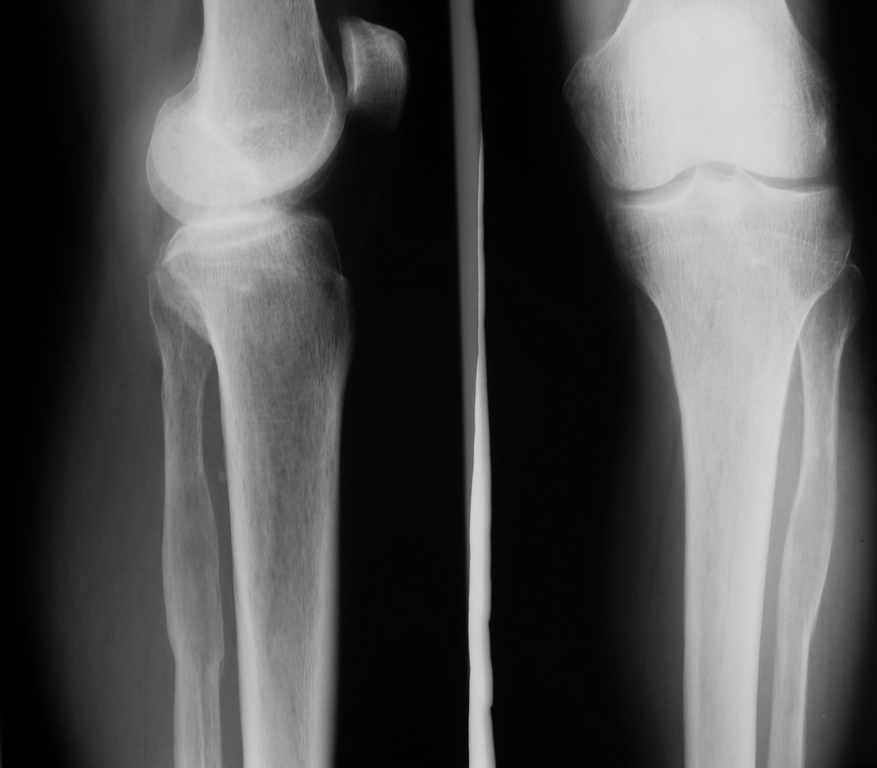

Всем привет!Кому интересно - может лицезреть мое личное наблюдение первичной костной лимфомы с поражением правой большеберцовой кости (см. аттач). Пациент: мужчина, 46 лет. Анамнез прослеживается в течение 1,5 лет - начало заболевания с появления болей.С уважением, Виталий Тазалов.

Ещё одно клиническое наблюдение - лимфома кости, до и после ПХТ и лучевой терапии.